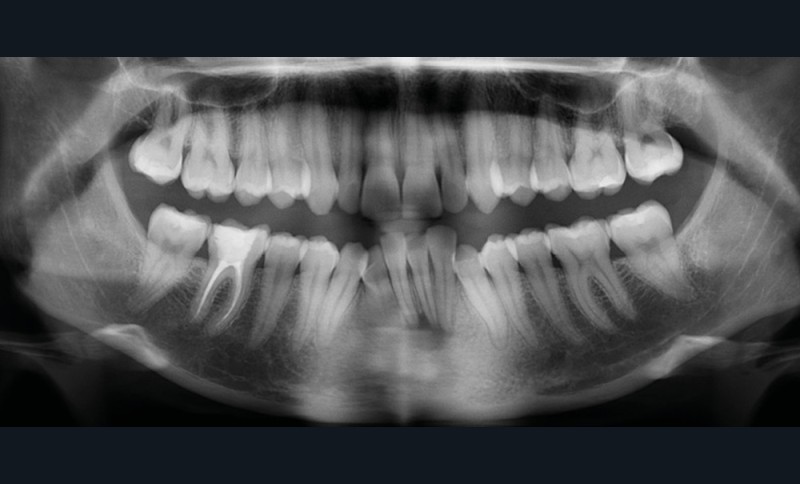

Examens complémentaires (fig. 3a,b)

À la radiographie panoramique, 31 présente une importante image apicale, confirmée par une radiographie rétroalvéolaire et également visible sur la téléradiographie de profil.

Cette dernière montre un schéma squelettique de Classe I et une typologie verticale normodivergente. Les rapports incisifs sont normaux et l’épaisseur des tissus mentonniers est insuffisante pour obtenir la fermeture buccale sans contraction. La symphyse est fine et l’incisive est centrée sur celle-ci.